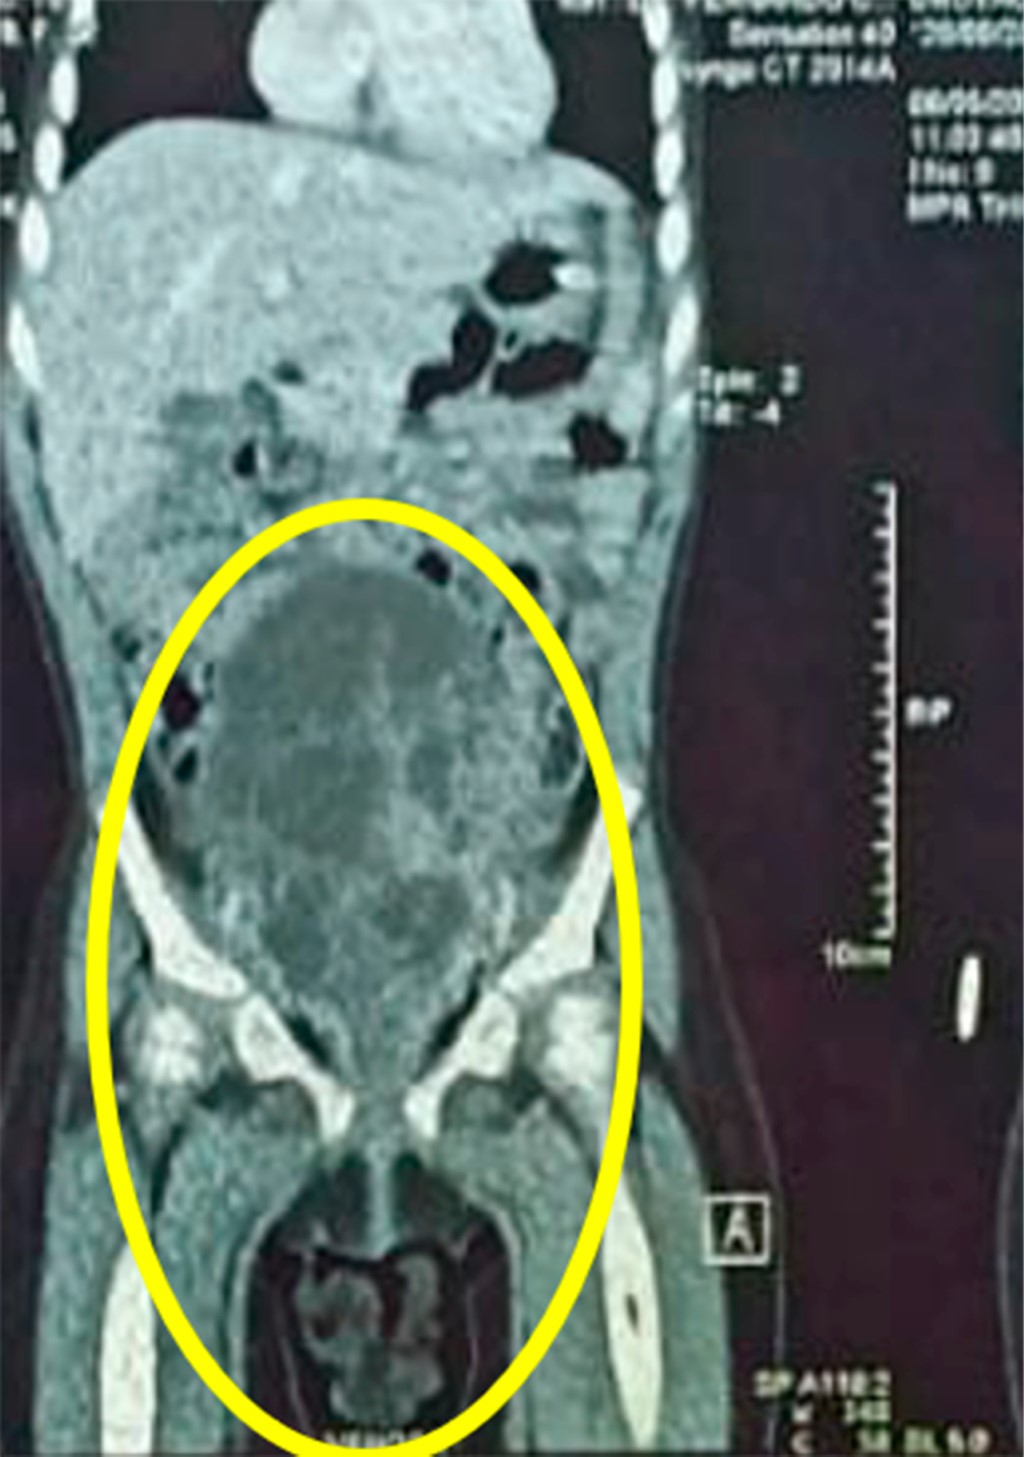

La paciente se hospitaliza para realizar tomografía; el estudio confirmó la presencia de una masa intravesical de 4 × 3 cm de diámetro y 5 × 3 cm de longitud, con lesiones hiperdensas con centros hipodensos (Figura 3); además se observaron ganglios linfáticos inguinales bilaterales de aspecto reactivo e hidronefrosis bilateral grado 2. Pero sin evidenciar metástasis a distancia (Figura 4).

Figura 3

Figura 4